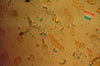

BIOPHOTO ASSOCIATES/SCIENCE PHOTO LIBRARY

CPP関節炎の診断は,偏光顕微鏡検査で複屈折性を示さないか弱い正の複屈折性を示す,菱形または桿状の結晶を滑液中に同定することで確定する。急性発作時の滑液には,典型的な炎症の所見がみられるため,感染性関節炎と痛風(滑液に炎症所見がみられる他の一般的な原因である)の同時発生も除外する必要がある。感染性関節炎は,グラム染色および培養の所見に基づいて除外する。痛風は,炎症を起こした関節から採取した液体中に尿酸結晶が検出されないことをもって除外するのが最良である。注意すべき点として,痛風とCPP関節炎が併発することもある。分析用の滑液を採取できない場合はX線または超音波検査の適応となり,関節軟骨(特に線維軟骨)に複数の線形または点状のカルシウム沈着所見を認めれば,診断の裏付けになるものの,痛風および感染症は除外できない。